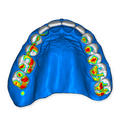

The DSD Interdisciplinary is a digital wax up of the upper and lower arches, designed considering a facially-driven, clinical and functional analysis of the patient.

Our 3D simulations showcase various treatment suggestions, facilitating a deeper understanding of the required procedures. This leads to the creation of a broader treatment plan and enables a more efficient communication with your patients.